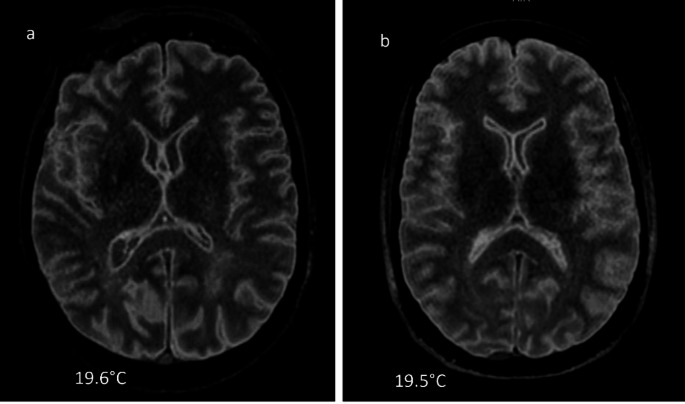

Materials and methods: 3D FLAIR sequences with varying TI values (from 1660 ms to 900 ms, every 110 ms) were acquired. Two radiologists independently assessed the images, selecting the TI that produced the most patient-like contrast. Rectal temperature and the DC-PMMR interval were recorded, and Pearson correlation tests were conducted to evaluate interrelations between TI, temperature, and DC-PMMR interval. Interobserver reliability was assessed using PABAK.

Result: Overall, 23 cases were analyzed. Rectal temperature ranged from 5.7 °C to 29.0 °C, and the DC-PMMR interval from 13.05 to 768 h. A moderate interobserver reliability (PABAK = 0.56) was observed. Significant correlations were observed between TI and both temperature (r = 0.70, p = 0.0014) and DC-PMMR interval (r = - 0.68, p < 0.0003).

Conclusion: Our empirical approach trends the results of previous studies: Postmortem 3D FLAIR contrast is significantly affected by the temperature and the DC-PMMR interval, suggesting that TI should be adapted accordingly.